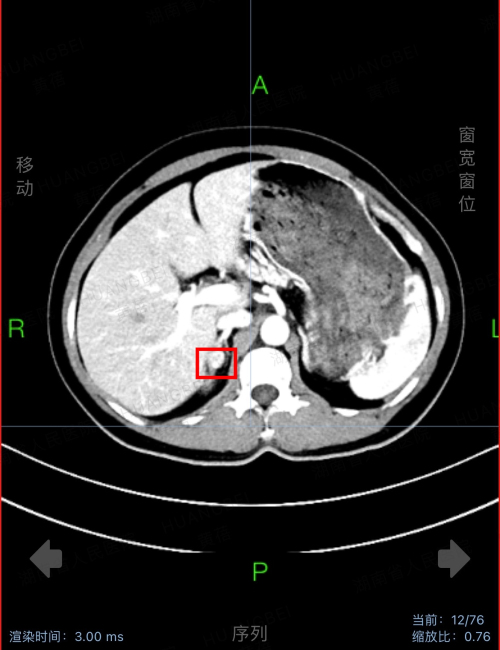

在ct下显示患者右侧肾上腺有一大小约42*30mm的结节

家住长沙的彭先生血压升高5年,反复四肢乏力1年多。入院后通过完善相关检查发现,患者为醛固酮增多症性高血压,还合并了低钾血症,且右侧肾上腺有一大小为42*30mm的结节。通过泌尿外科实施了腹腔镜下右侧肾上腺肿瘤切除,术后复查24小时动态血压达标,血钾也恢复正常。